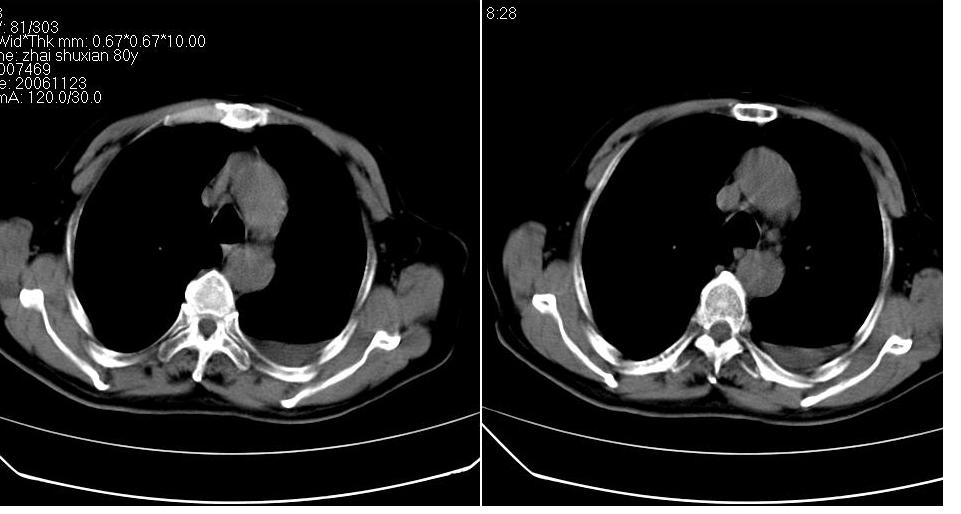

左下肺体积缩小,密度增高,见片增密影。边界模糊,见支气管充气像,肺门纵隔无异示,心脏气管左移,左侧胸腔少量积液。考虑肺部感染伴部分肺不张[有脑梗塞病史坠积性肺炎可能]

1、左肺下叶后基底段炎症并膨胀不全。

2、左侧胸腔积液。

左肺下叶体积缩小,成类楔形软组织影,其内可见部分含气支气管影,相应左侧肺门区未见明显肿块,考虑炎性病变,建议抗炎后短期复查

3.两肺慢支改变。

左下肺体积缩小,密度增高,并见大片状致密影,边界模糊,其内见支气管充气像,肺门纵隔无异常,心脏气管左移,左侧胸腔少量积液。考虑:左肺炎性病变伴不张。